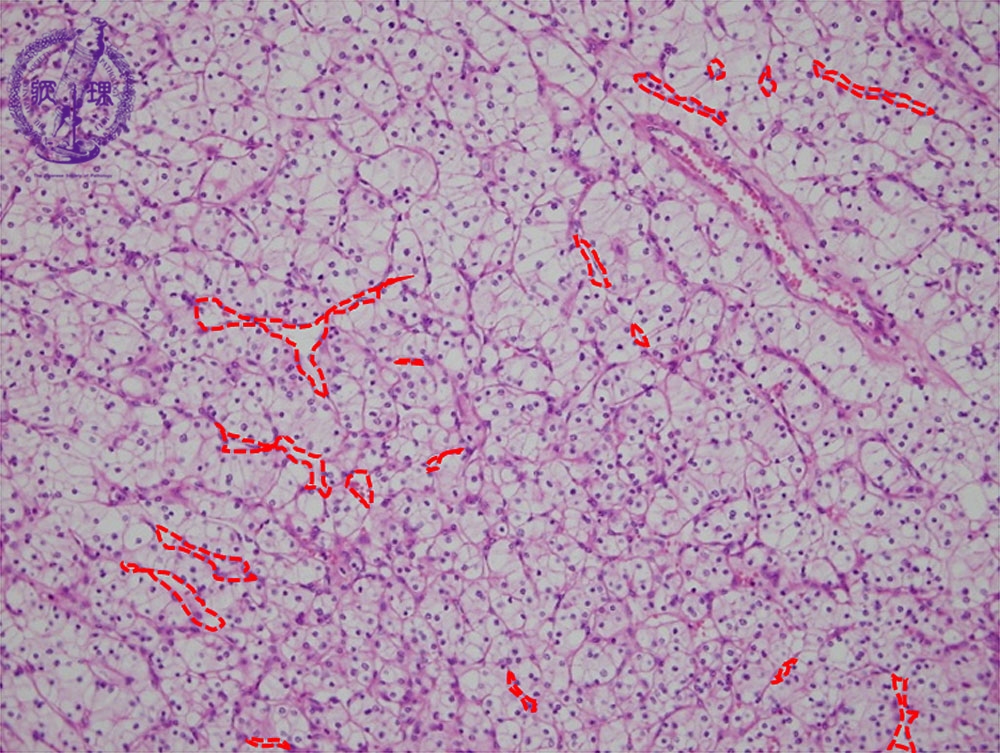

- ★(17)Renal cell carcinoma

Microscopic findings ( HE, middle power view): Renal cell carcinoma (clear cell carcinoma). The tumor cells are arranged in an alveolar manner associated with a fine sinusoid-like capillary network (red dotted lines).